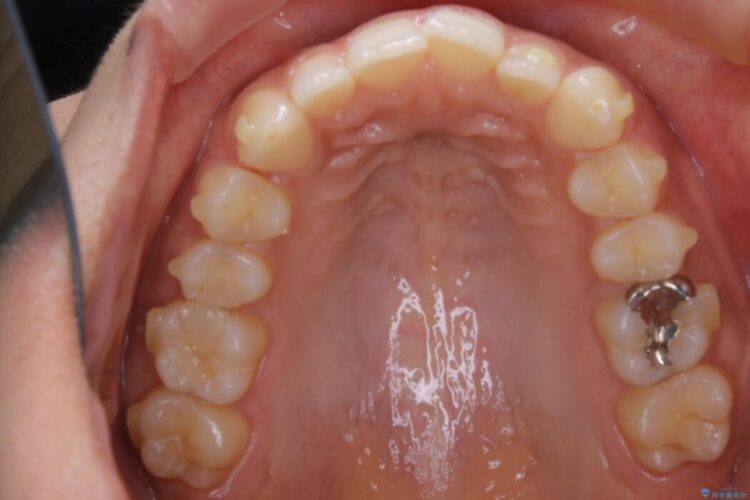

叢生の度合いにより抜歯は不要と判断しましたので、歯列幅の拡大を主軸に置き矯正治療を行いました。

本症例では下顎の歯列が舌側へ傾くことにより幅が狭まっていましたので、マウスピース治療により歯列弓を拡大しました。